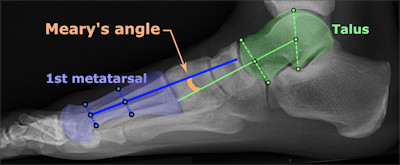

Radiologisch als een denkbeeldige as die door het midden van de talus wordt

getrokken, loodrecht op het gewrichtsvlak, niet uitkomt in het midden van het

eerste metatarsale bot van dig I. Normaal als de botten netjes in elkaars verlengde

staan hoort men een rechte lijn te kunnen trekken door metatarsale 1 en de tarsus.